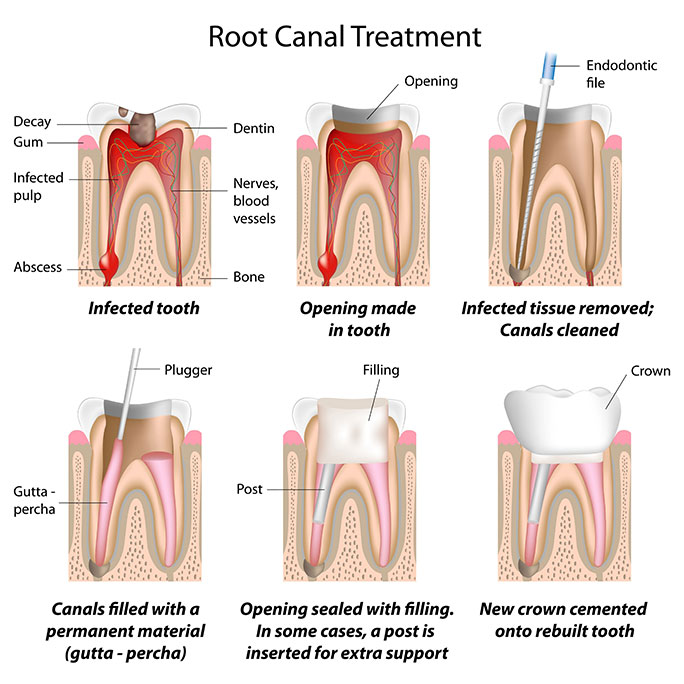

What Are the Steps in Root Canal Treatment?

- The decay is first removed. An opening is made at the top of the tooth.

- Damaged pulp tissue is removed from the pulp chamber and root canals.

- Canals are thoroughly cleaned and disinfected. Sometimes, medication is placed in the canals, and the opening is temporarily filled until the next appointment.

- Canals are sealed with a biocompatible material, and the tooth opening is filled permanently (core). If the tooth is badly damaged, a post may be inserted to retain the core.

- To protect back teeth (premolars and molars), a crown is recommended after root canal treatment. Severely damaged front teeth may also require crowns.